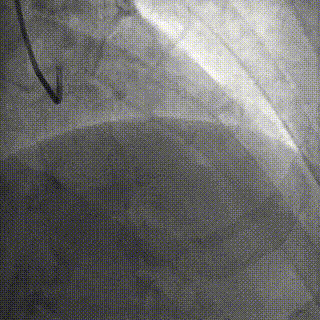

手术影像

LAD、LCX双支 CTO ,LAD 近端50%狭窄

RCA粗大,支架代偿良好。远端60%狭窄,PDA开口80%狭窄

策略讨论:双支CTO,闭塞段残端清晰,钙化,右冠造影可见PLV/PDA侧供LCA。由于有前降支PCI失败史,该次已经做好充分准备,大概率需要逆向PCI。